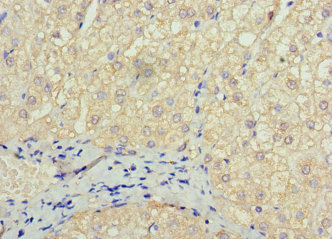

Immunohistochemistry of paraffin-embedded human liver cancer using CSB-PA022422LA01HU at dilution of 1:100